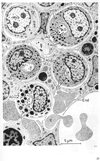

洞様血管;類洞;洞【どうようけっかん;るいどう】 Specially formed segment of a vessel with thin walls and a larger lumen.(類洞は洞様毛細血管ともいう。肝小葉の内部で肝細胞板の間隙に分布する毛細血管。吻合分枝して全体として網状を呈する。1層の薄い内皮臍傍よりなる壁で限界されるが、一般毛細血管より径が大きく類洞と呼ばれる。肝動脈枝と門脈枝は小葉の周辺において類洞へ移行し、動脈血と門脈血が混ざり合い類洞内を小葉中心方向へ流れ中心静脈にそそぐ。この間、ガス交換や栄養分の授受を行い、解毒作用や産生された血清蛋白を受ける。肝細胞板との間には類洞周囲隙が存在し、血液の液性成分は内皮細胞にある大小の孔を通って類洞周囲隙と交流巣売る。類洞内腔には貪食性のKupffer細胞がみられる。類洞壁の外側にはビタミンAを取り込む類洞周囲脂質細胞が付着している。)